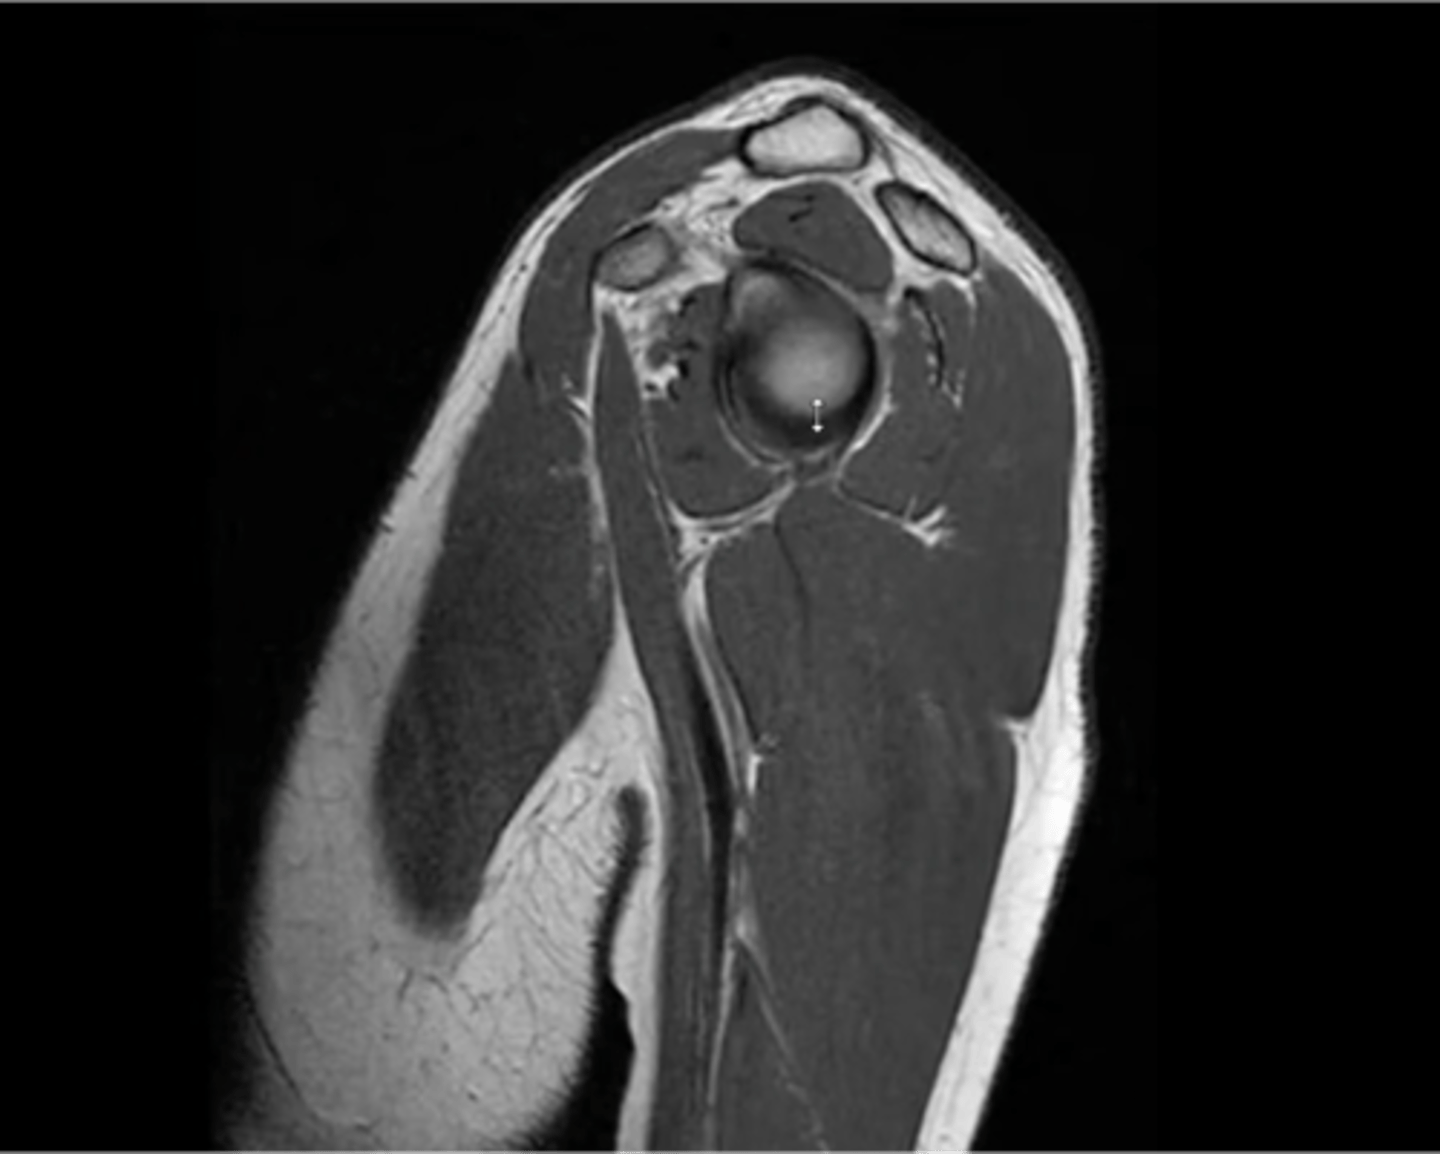

Os Acromiale, a disorder that involves lack of fusion of the acromion (i.e., the growth plate did NOT fuse --> mobile acromion --> encroachment and impingement on the rotator cuff tendons)

What are these images depicting at the ACJ?